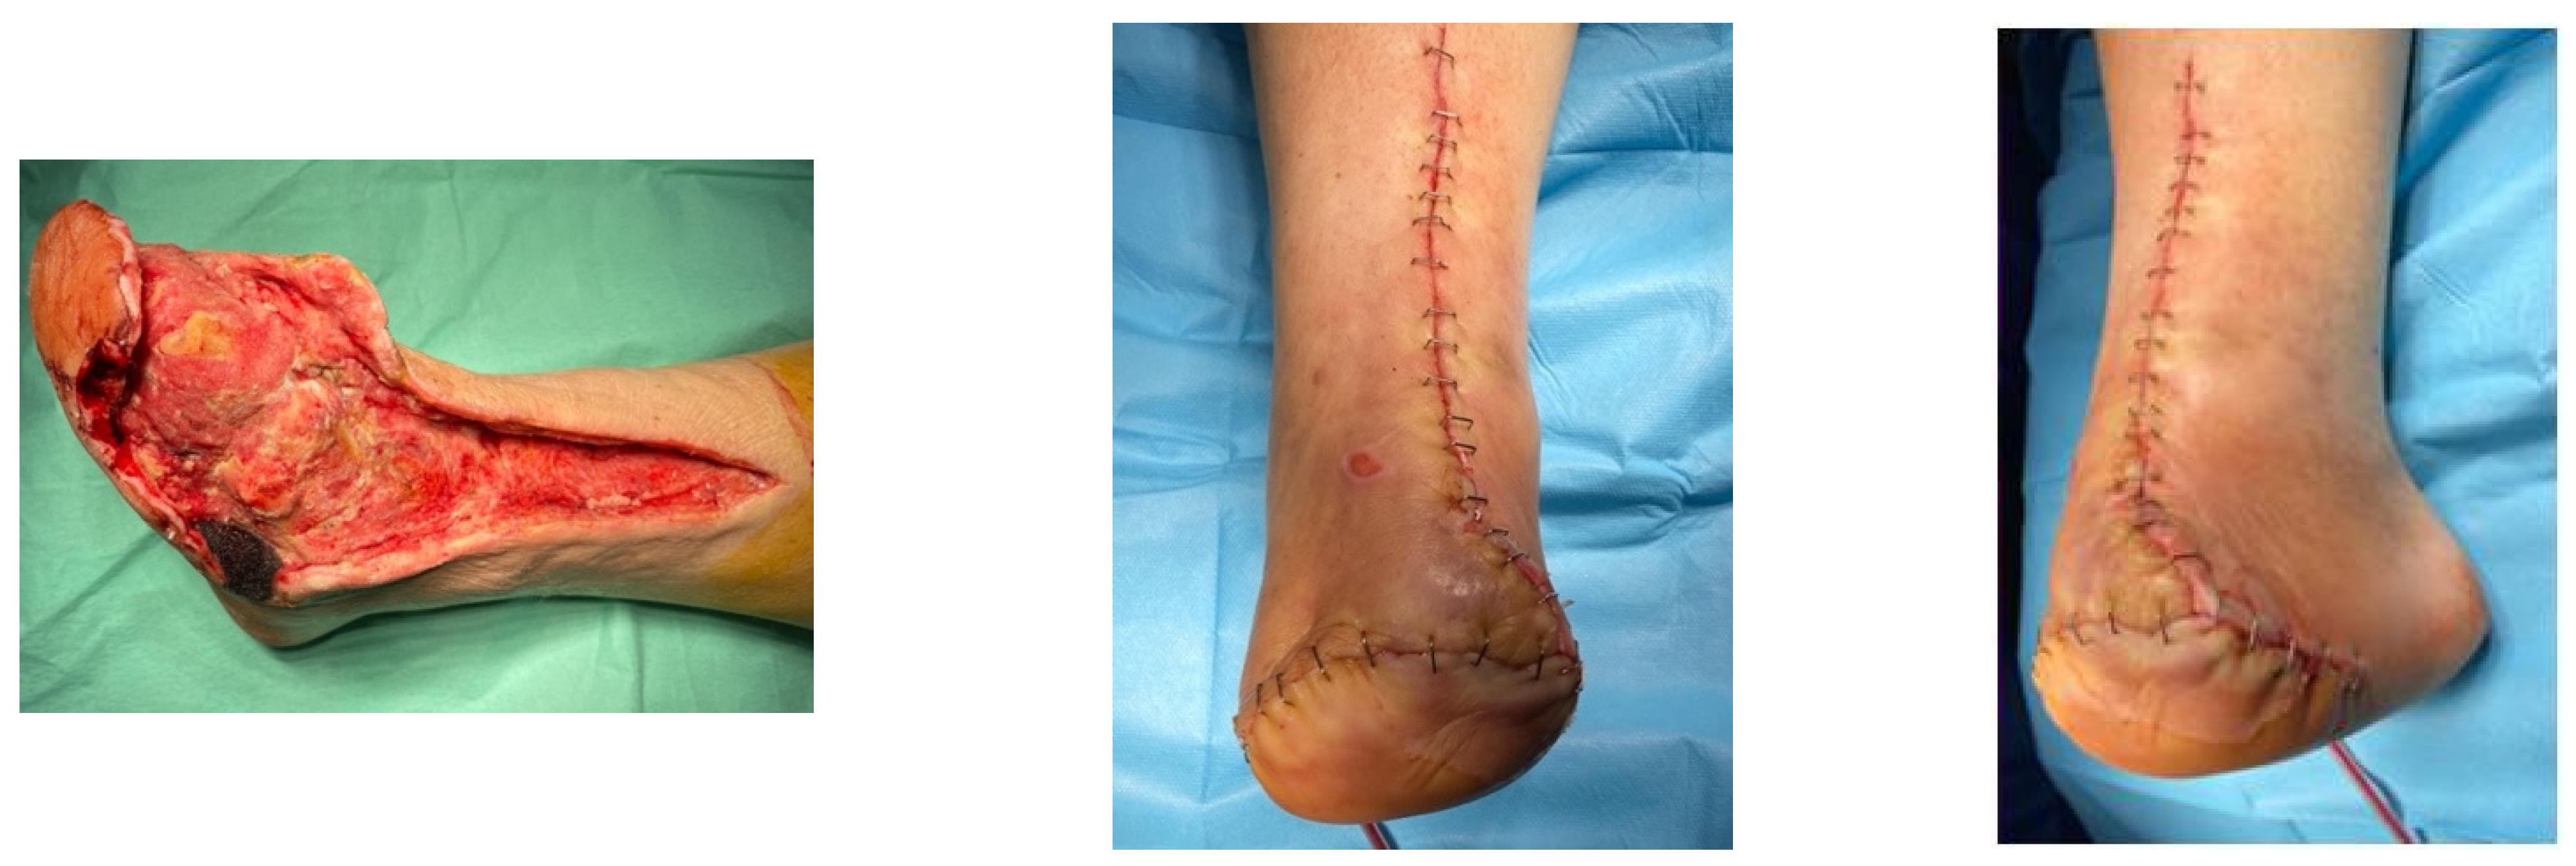

4.1. Case 1—Direct Revascularization-Minor Amputation

4.2. Case 2—Indirect Revascularization-Major Amputation